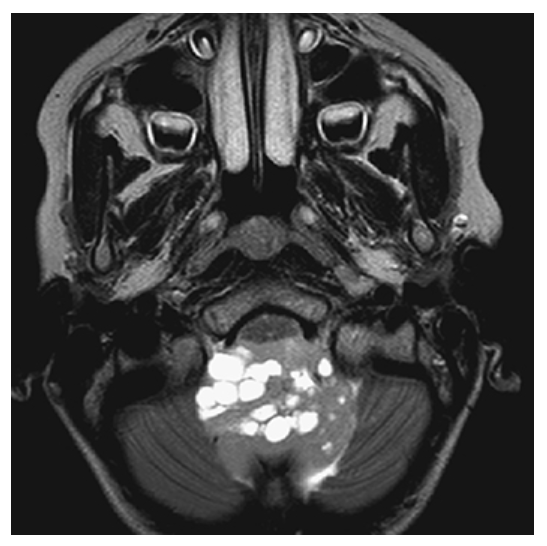

Meningioma. Noncontrast CT shows round, high-density mass over the convexity of the right parietal lobe.

Meningioma. Postcontrast CT image shows a round, markedly contrast-enhancing mass over the convexity of the right parietal lobe.